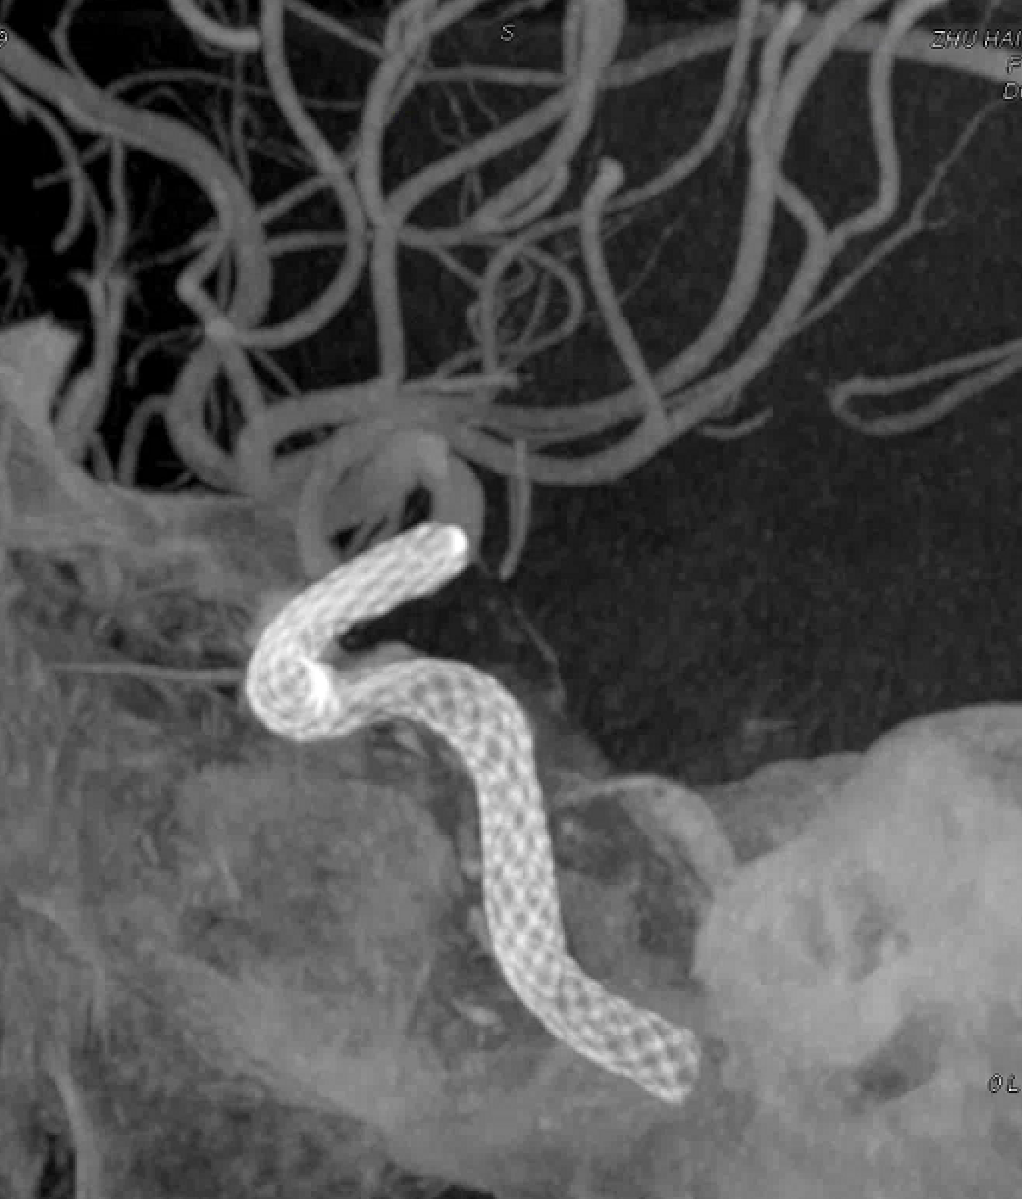

左侧瘤体形态欠规则,4mm×30mm Streamline 优先处理左侧动脉瘤

术后3月复查,瘤体未见显影,载瘤动脉通畅

同期4mm×20mm Streamline 进一步处理右侧动脉瘤